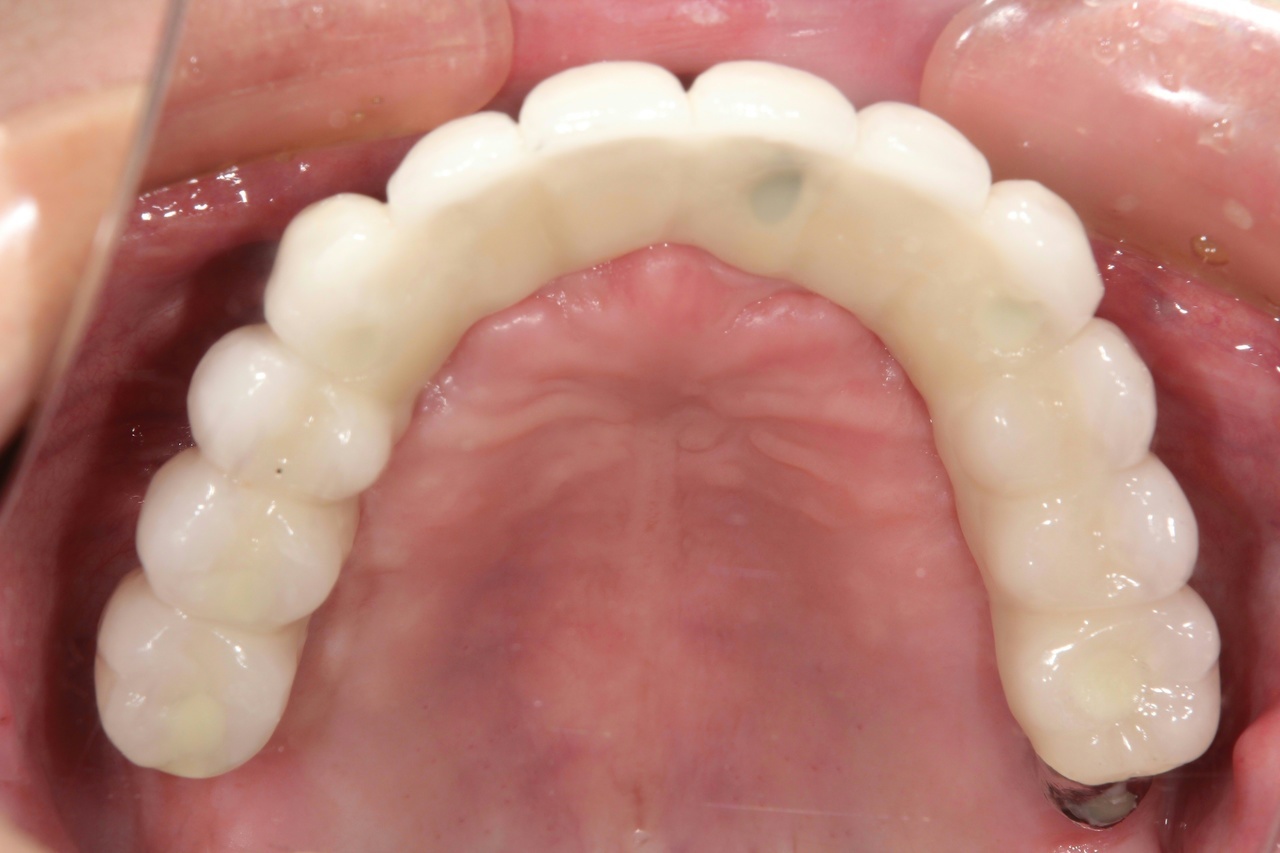

最終的な被せ物装着

インプラントがしっかり骨に定着したら、型取りをして、最終的な被せ物を製作し、装着します。

(今回は下顎ですが、その前に上顎は治療済みです。)